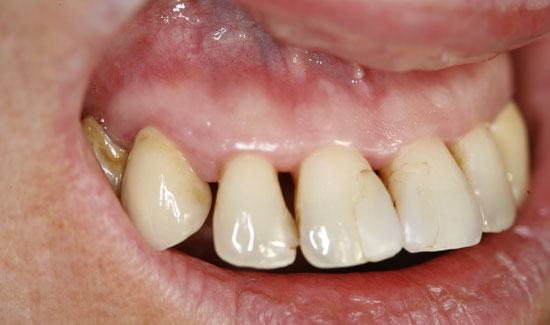

Fig. 3: Condition after ozone therapy. Chlorhexidine staining of the teeth

The patient introduced herself at our practice, inquiring about preserving the front teeth of her upper jaw, which were suffering from chronic periodontitis. We discovered general formation of pockets

(> 10 mm), spontaneous bleeding and a degree of tooth mobility of 2/3, i.e. the teeth were candidates to be extracted. As an interim solution (it was a public holiday) until restoration could take place, we offered local ozone gas treatment.

As an ozone gas source, we used Prozone, which, with the aid of plastic attachments, makes it possible to introduce ozone gas into the pockets in a pain-free manner. The local application of ozone gas was repeated three times, at weekly intervals. The patient was also made aware of necessary personal hygiene measures. Not only were we able to stop the bleeding, but we were also able to keep the degree of mobility of the teeth at a stable level (2) and reduce the measurable depth of the pockets.